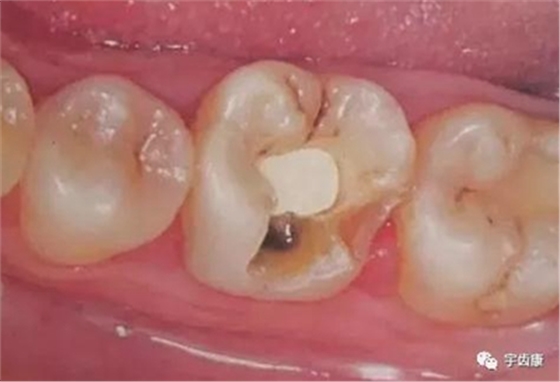

防止過度預(yù)備(造成牙髓激惹)

保留活髓(保留牙體的整體性和韌性)

過度預(yù)備抗力形喪失